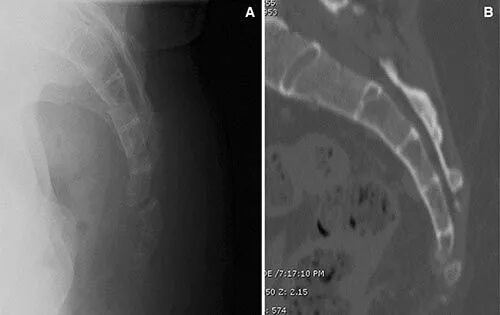

Снимок копчика